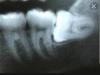

Вот у меня примерно так же. Соседний зуб давит и больно. Фото из интернета в комментариях. Куда ехать?

@kras_styu, ну вообще да , сделать снимок нужно в проекции . Всю челюсть , и там будет видно как лежит зуб и решат как удалять . Такое удаление считается как операция . Назначат сразу какие лекарства нужны будут , вас запишут на день удаления . За пару дней начнете пить антибиотики, а там уже и обезбол будет дней 10 еще .

С такой 8кой надо прям хорошего хирурга. Есть риск вытянуть вместе с 7кой, при таком удалении надо как можно меньше травмировать десну. Высок риск флюса. Мне так Бородин объяснял, почему он мне его и долго тянул, почему и десну совсем чуть-чуть надрезал, пытался выкрутить его как-то.